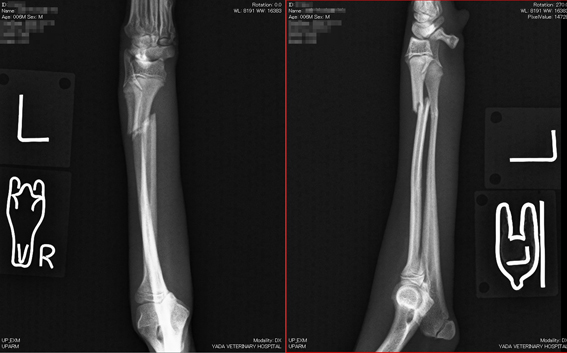

トイプードル

体重1.8kg、1歳4か月齢

左橈尺骨遠位の骨折。

写真1段目: 手術前

写真2段目: 手術後

写真3段目: ピン抜去直後

手術後1か月半で抜ピンしました。

写真4段目: ピン抜去1か月後